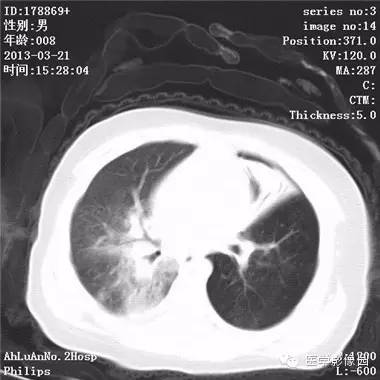

影像学表现